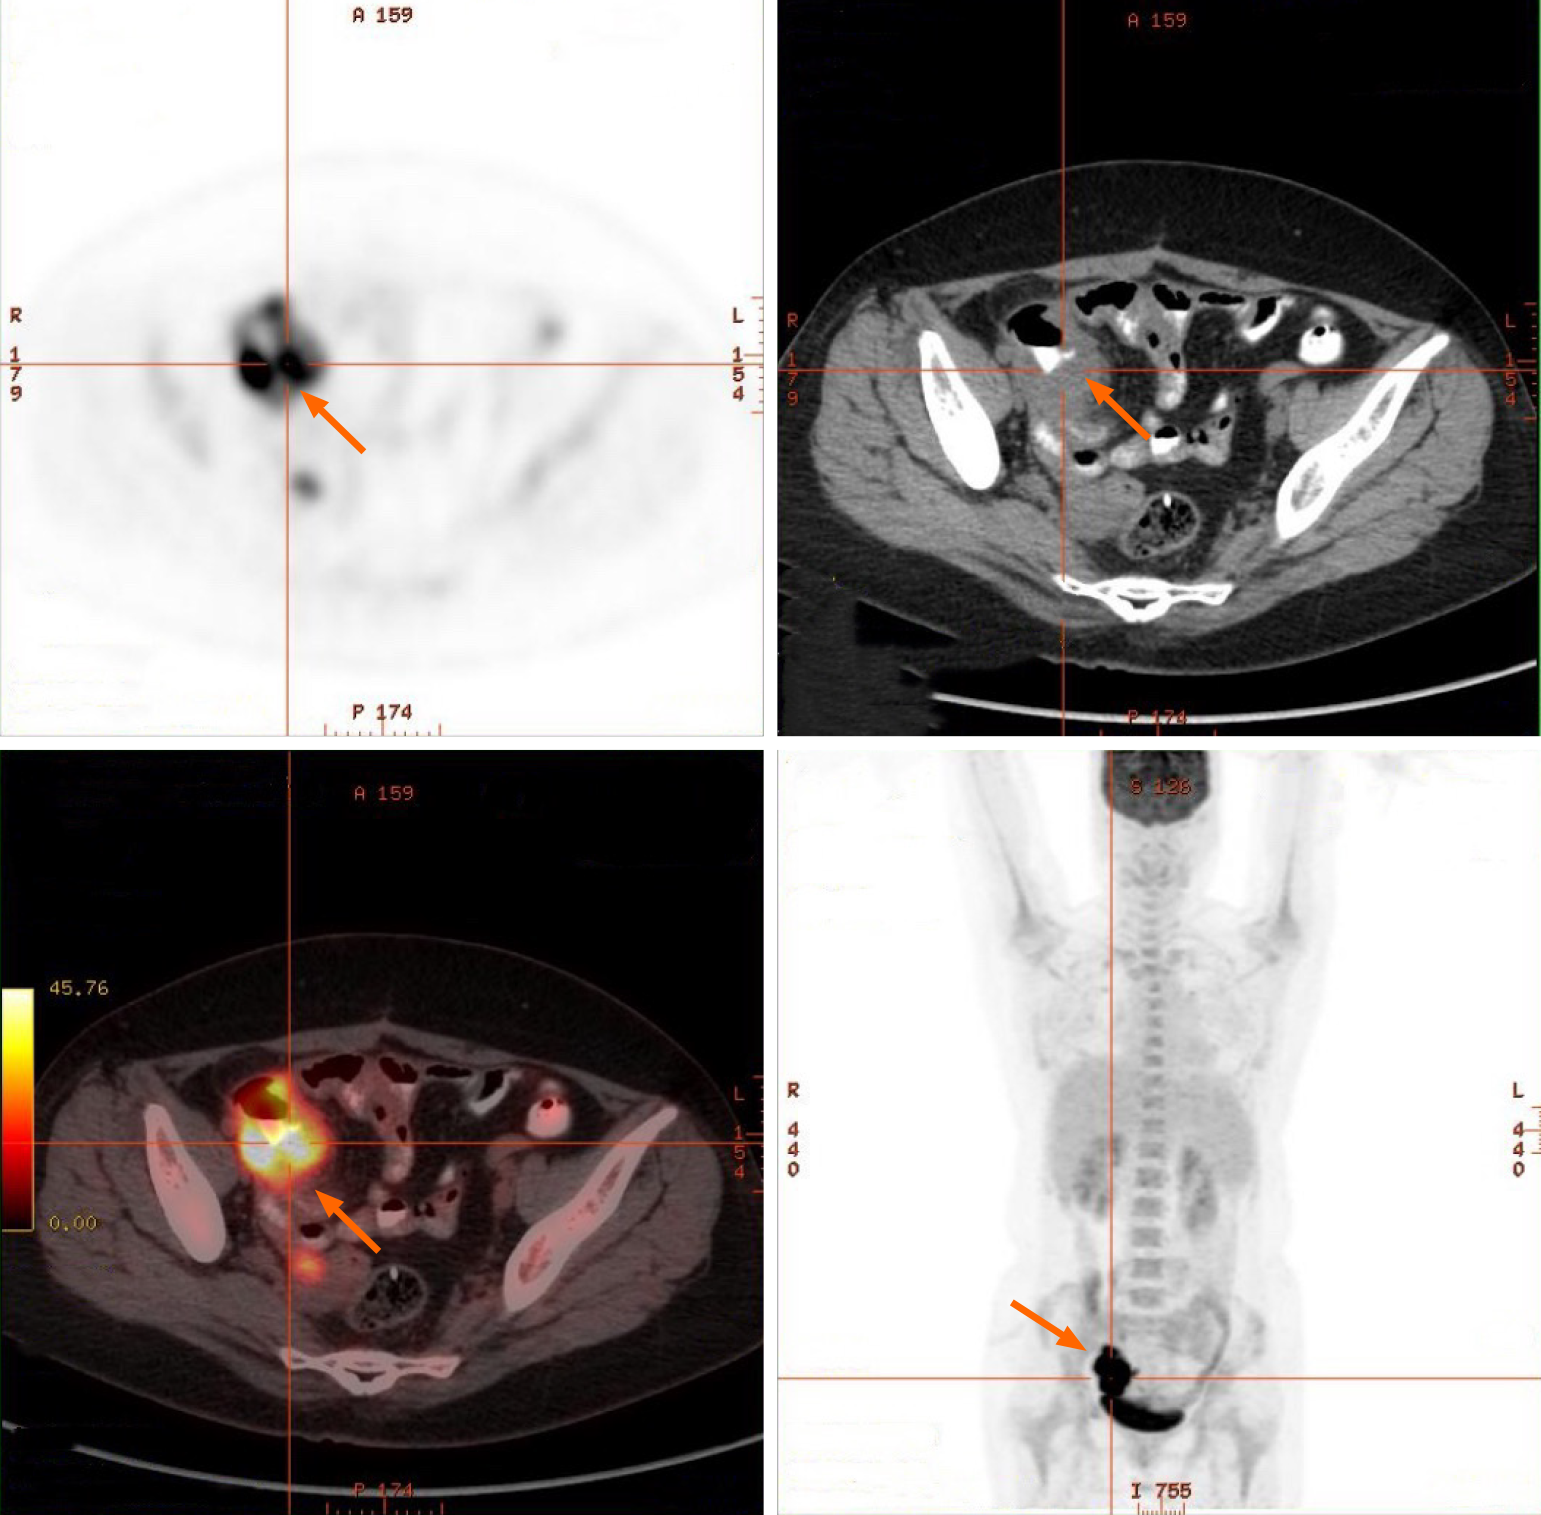

Figure 1 Small intestine positron emission tomography/computed tomography images.

Positron emission tomography/computed tomography revealed localized thickening of the small intestinal wall in the right pelvic region with increased metabolic activity, suggestive of implantation metastasis. The arrows point to the focal area of intestinal wall thickening with high metabolic activity.